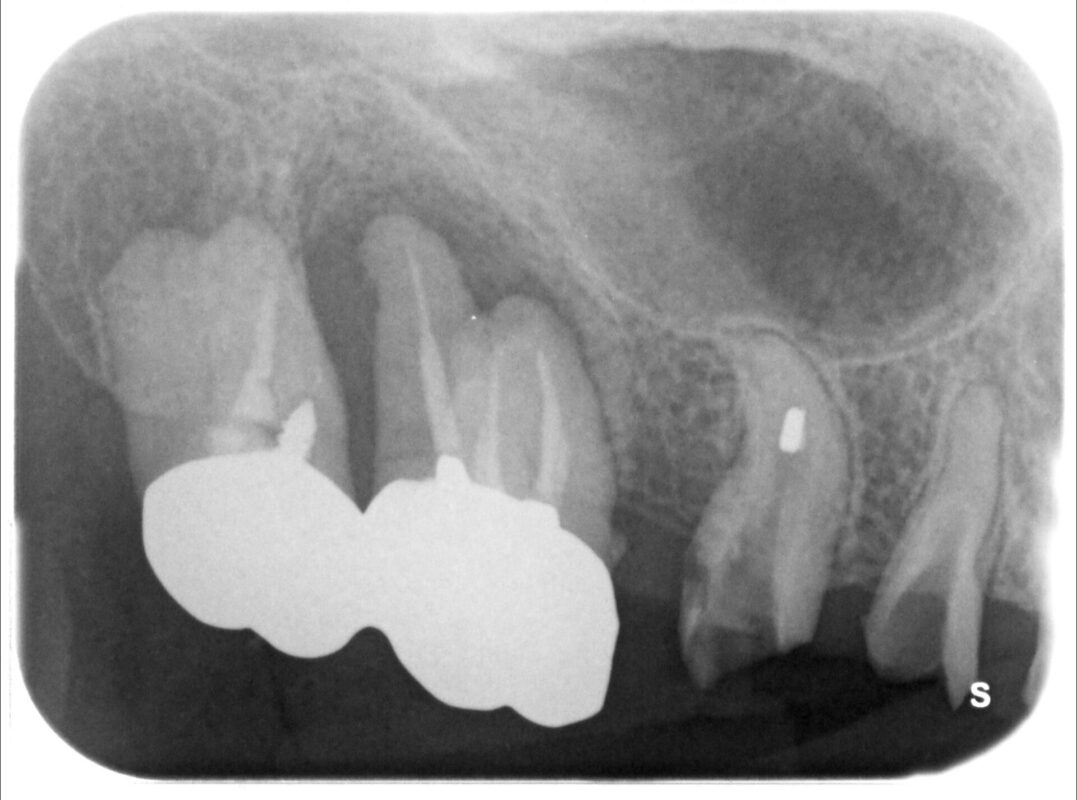

術前

術前のCT検査などで、インプラント治療をご希望されるものの骨が全くなく、このままでは治療不可能

です。

術前の検査で最初一回法によるインプラント治療を計画しました。

高さ不足解消のためにサイナスリフトを伴うインプラント治療の場合、1回で行うことが多いのです

が、この患者さんは幅も狭かったので、まず骨のある程度の厚みと高さを確保する処置を行いました。